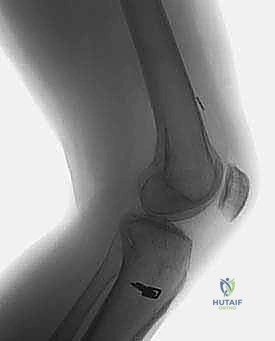

* الأشعة السينية (X-rays): ضرورية لتقييم اتساع الأنفاق العظمية السابقة (Tunnel Widening)، مواقع مسامير التثبيت القديمة، ووجود أي علامات لخشونة المفصل أو انحراف محوري.

* الأشعة المقطعية (CT Scan): في حالات الفشل الجراحي، تعتبر الأشعة المقطعية السلاح الأهم. فهي توفر نمذجة ثلاثية الأبعاد (3D) دقيقة جداً لمواقع الأنفاق العظمية القديمة وحجمها، مما يساعد الدكتور هطيف في اتخاذ قرار حاسم: هل يمكن حفر أنفاق جديدة فوراً، أم يجب إجراء الجراحة على مرحلتين؟